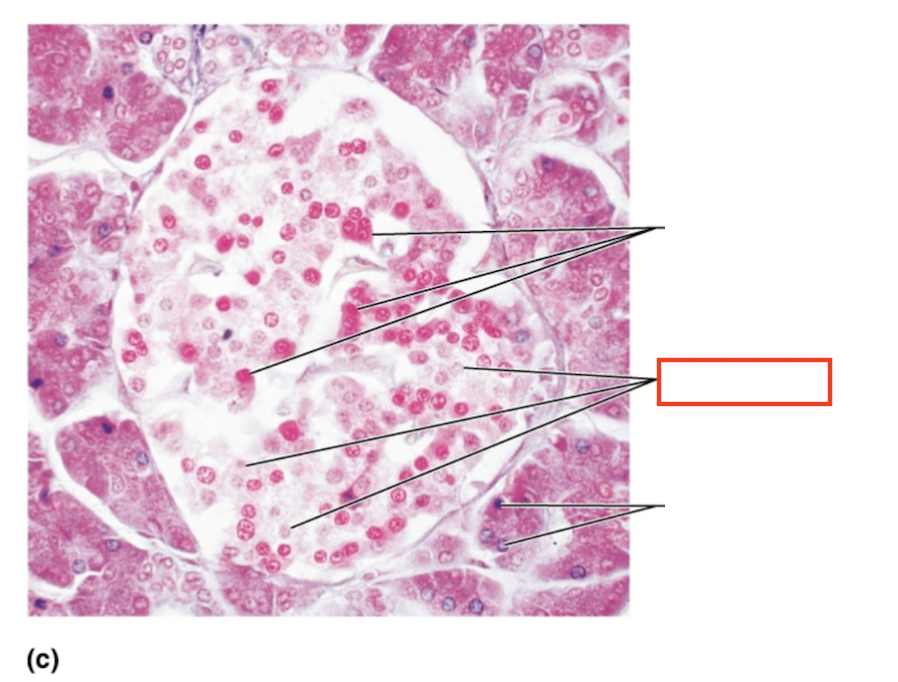

What structure is highlighted?

alpha cells (glucagon producing)

What structure is highlighted?

beta cells (insulin producing)

What structure is highlighted?

pancreatic acinar cells (exocrine)

What tissue is shown?

pancreatic islet

What hormones are released by the pancreas?

insulin, glucagon

What are the target organs and effects of insulin

most cells of the body, accelerates the transport of glucose into body cells; promotes glycogen, fat, and protein synthesis

What are the target organs and effects of glucagon?

primarily the liver and adipose; accelerates the breakdown of glycogen to glucose, stimulates the conversion of lactic acid into glucose, releases glucose into the blood from the liver

What stimulates glucagon production?

decreased blood glucose levels, sympathetic nervous system stimulation

What stimulates insulin production?

increased blood glucose levels, parasympathetic nervous system stimulation